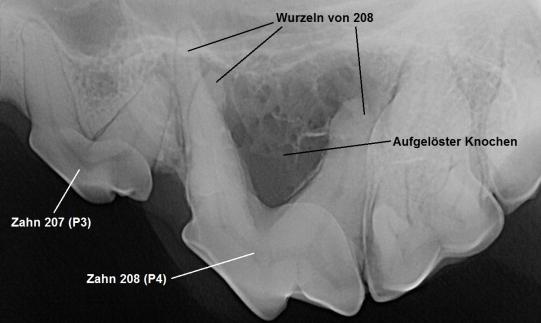

Jessy wird sobald als möglich narkotisiert und genauer untersucht. Die Schwellung am Oberkiefer scheint innert wenigen Tagen noch grösser geworden zu sein. Das Zahnfleisch um den P4 scheint auch etwas gerötet; ein Röntgenbild der Region zeigt, dass um die drei Wurzeln des Zahnes ein starker Knochenverlust stattgefunden hat, was die Verdachtsdiagnose Wurzelabszess bestätigt.